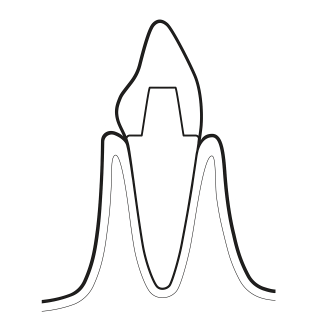

06 PIEZON® PS

Remove remaining calculus:

- Use the minimally invasive EMS PS instrument supra-and sugingivally up to 10 mm

- Clean > 10 mm pockets with mini curette

- Use EMS PI Instrument around implants up to 3 mm subgingivally and on restorations